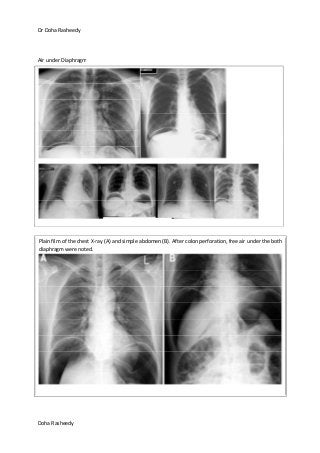

Air under Diaphragm

Plain film of the chest X-ray (A) and simple abdomen (B). After colon perforation, free air under the both

diaphragm were noted.